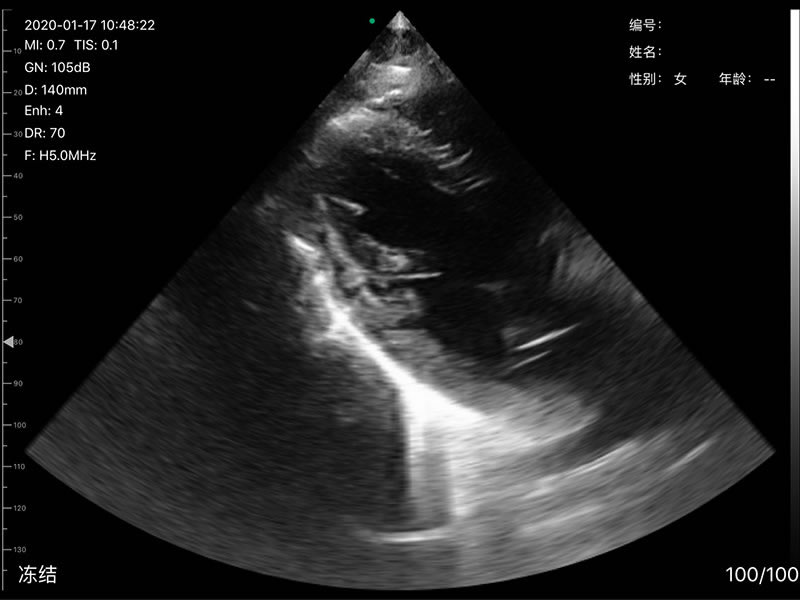

• 探头频率:凸阵/相控阵3.2/5.0MHz,线阵7.5/10MHz,心脏模式3.2-5MHZ

• 扫描深度:凸阵90/160/220/305mm,相控阵90/120/140/160,线阵20/40/60/80mm,可调

• 扫描角度和宽度:凸阵60°,相控阵80°,线阵宽度40mm

• 显示模式:B、B/M、Color、PW、PDI